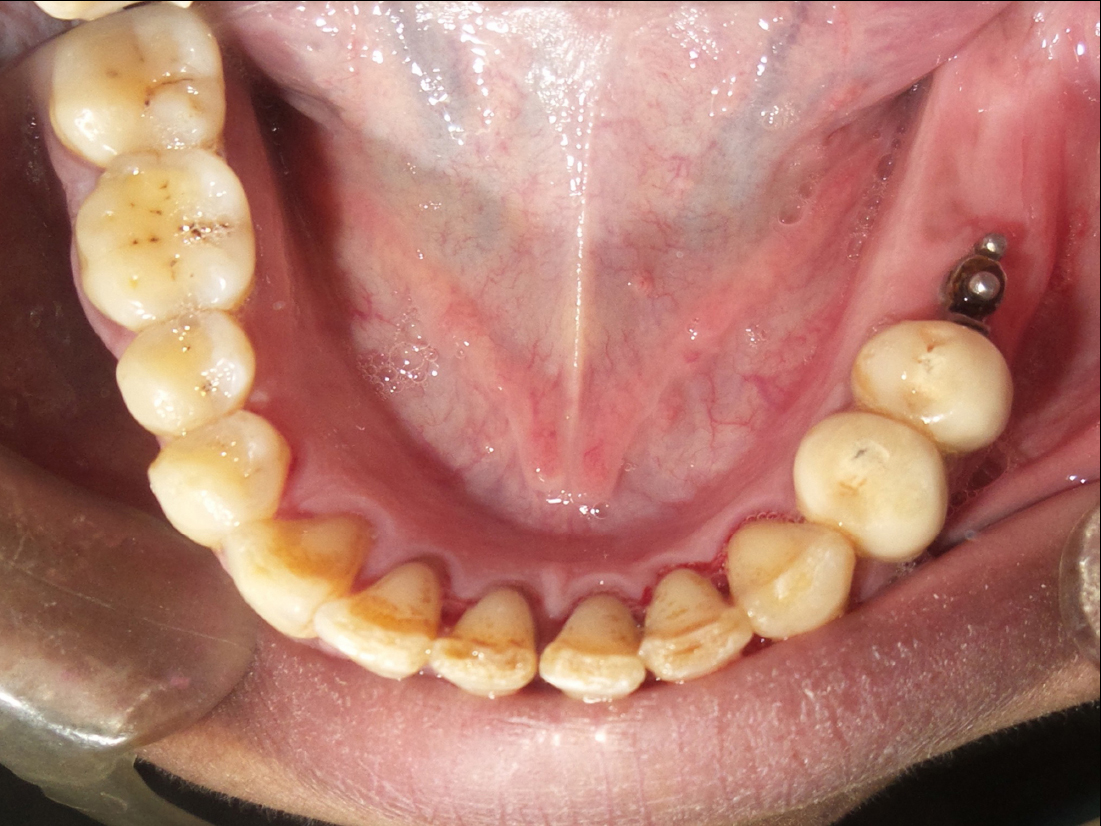

A vacuum stent surgical guide was made for each patient to be used during the surgery to determine the position of implant installation; Anesthesia (Inibsa Artinibsa 4%, Spain) was given, then the surgical guide was placed in the patient's mouth, and the probe was used to mark the proposed site for implant placement. A crystal incision was made extending 5 mm mesial and distal to the marked implant site. A full-thickness mucoperiosteal flap was reflected. The implant osteotomy of 10 mm length and 3.6 mm diameter was sequentially drilled, then the implant (Superline; Dentium, Korea) was installed in the osteotomy site (Fig. 2), and its cover screw was tightened, and the flap was sutured. After three months, the healing abutment was screwed to the implant and left for ten days for gingival healing and formation of the gingival collar and then replaced by the final abutment. The first and second premolar teeth in the distal extension side were reduced and prepared with sub-gingival finishing lines ready for crowing (Fig. 3). The final impression was made using a rubber base after changing the final abutment with impression-transfer (closed tray). Composite temporary (Protemp™ Plus, USA) crowns were made, then finished, polished, and cemented temporarily.

Fig. (3). Prepared first and second premolar with implant.